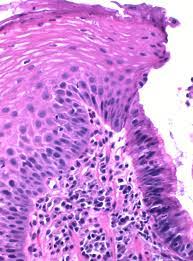

역류성 식도염이란?

위식도 역류성 질환은 위 내용물이 소량씩 식도로 역류하고, 이러한 역류의 과정이 반복되어 식도 점막이 손상되어 염증이 나타나는 질환을 의미합니다. 이는 위와 식도 사이에서 위의 내용물이 식도로 올라오는 것을 막아 주는 조임쇠 역할을 하는 괄약근에 이상이 생겨 발생합니다.